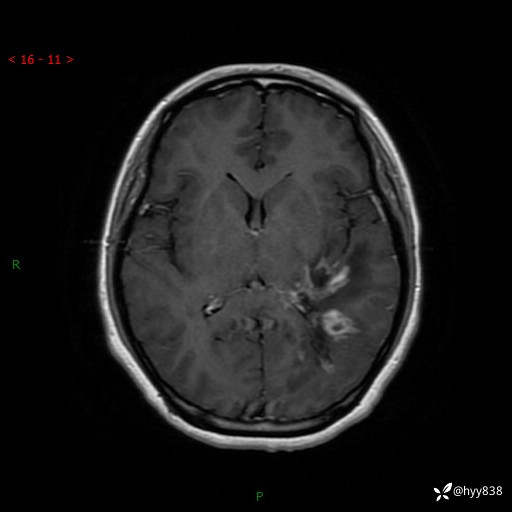

颅脑MRI平扫+增强